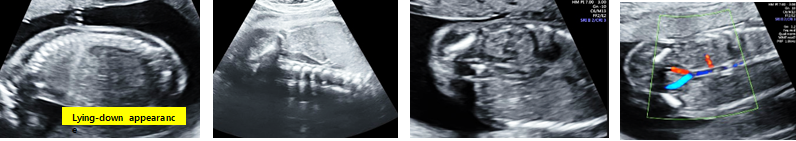

C. Invisible kidney

: 다음의 그림과 같이 sagittal view에서 renal fossa가 비어 있어 adrenal gland의 위치와 모양이 바뀌어 lying-down appearance를 관찰할 수 있습니다. 그 외 반대편 kidney는 hypertrophy해 보이며, coronal view에서 renal artery가 한 쪽이 없음을 같이 관찰할 수 있습니다.